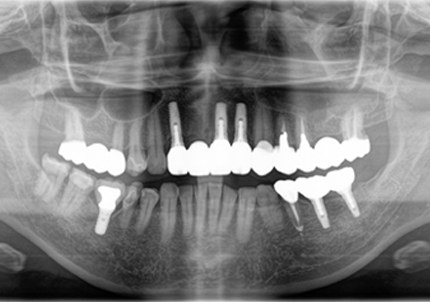

18.インプラント埋入後 パノラマレントゲン

10.口腔内写真(2022年2月)

特に問題無く経過はとても良いです。

患者様ご本人も「良く咬めてとても良い」と満足されています。

11.口腔内写真(2025年6月)

右下2本初診より9年経過、左下3本埋入後4年経過、ともに経過良好。